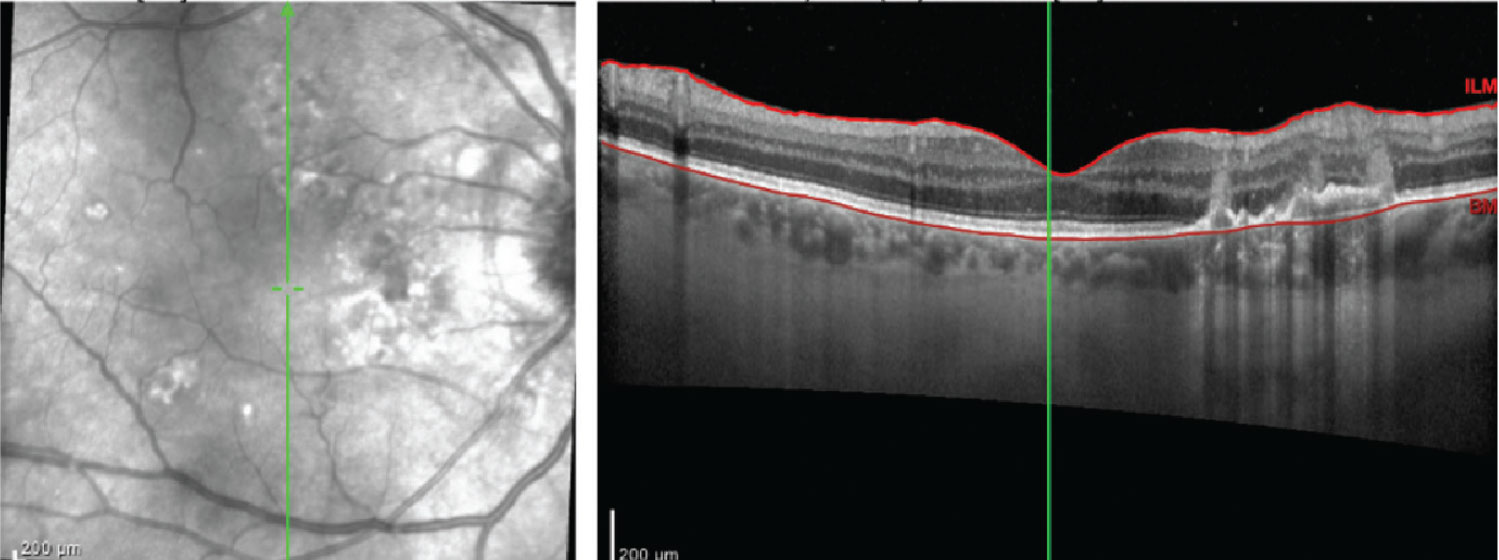

Optical coherence tomography of the right eye showed multiple focal and confluent retinal pigment epithelium elevations in a dome shape (Figure 3).

![]() |

Figure 3. Optical coherence tomography imaging of the right eye at time of initial presentation shows multiple focal and confluent retinal pigment epithelium elevations in a dome shape. |